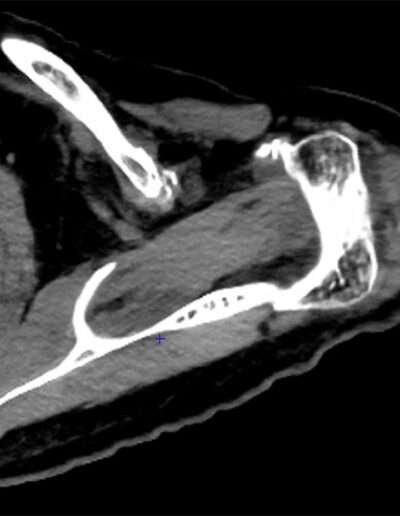

T06: TSA V-Shape

SHOULDER CASE SUMMARY:

Shoulder Left

Patient 81 y/o, Female, right-handed